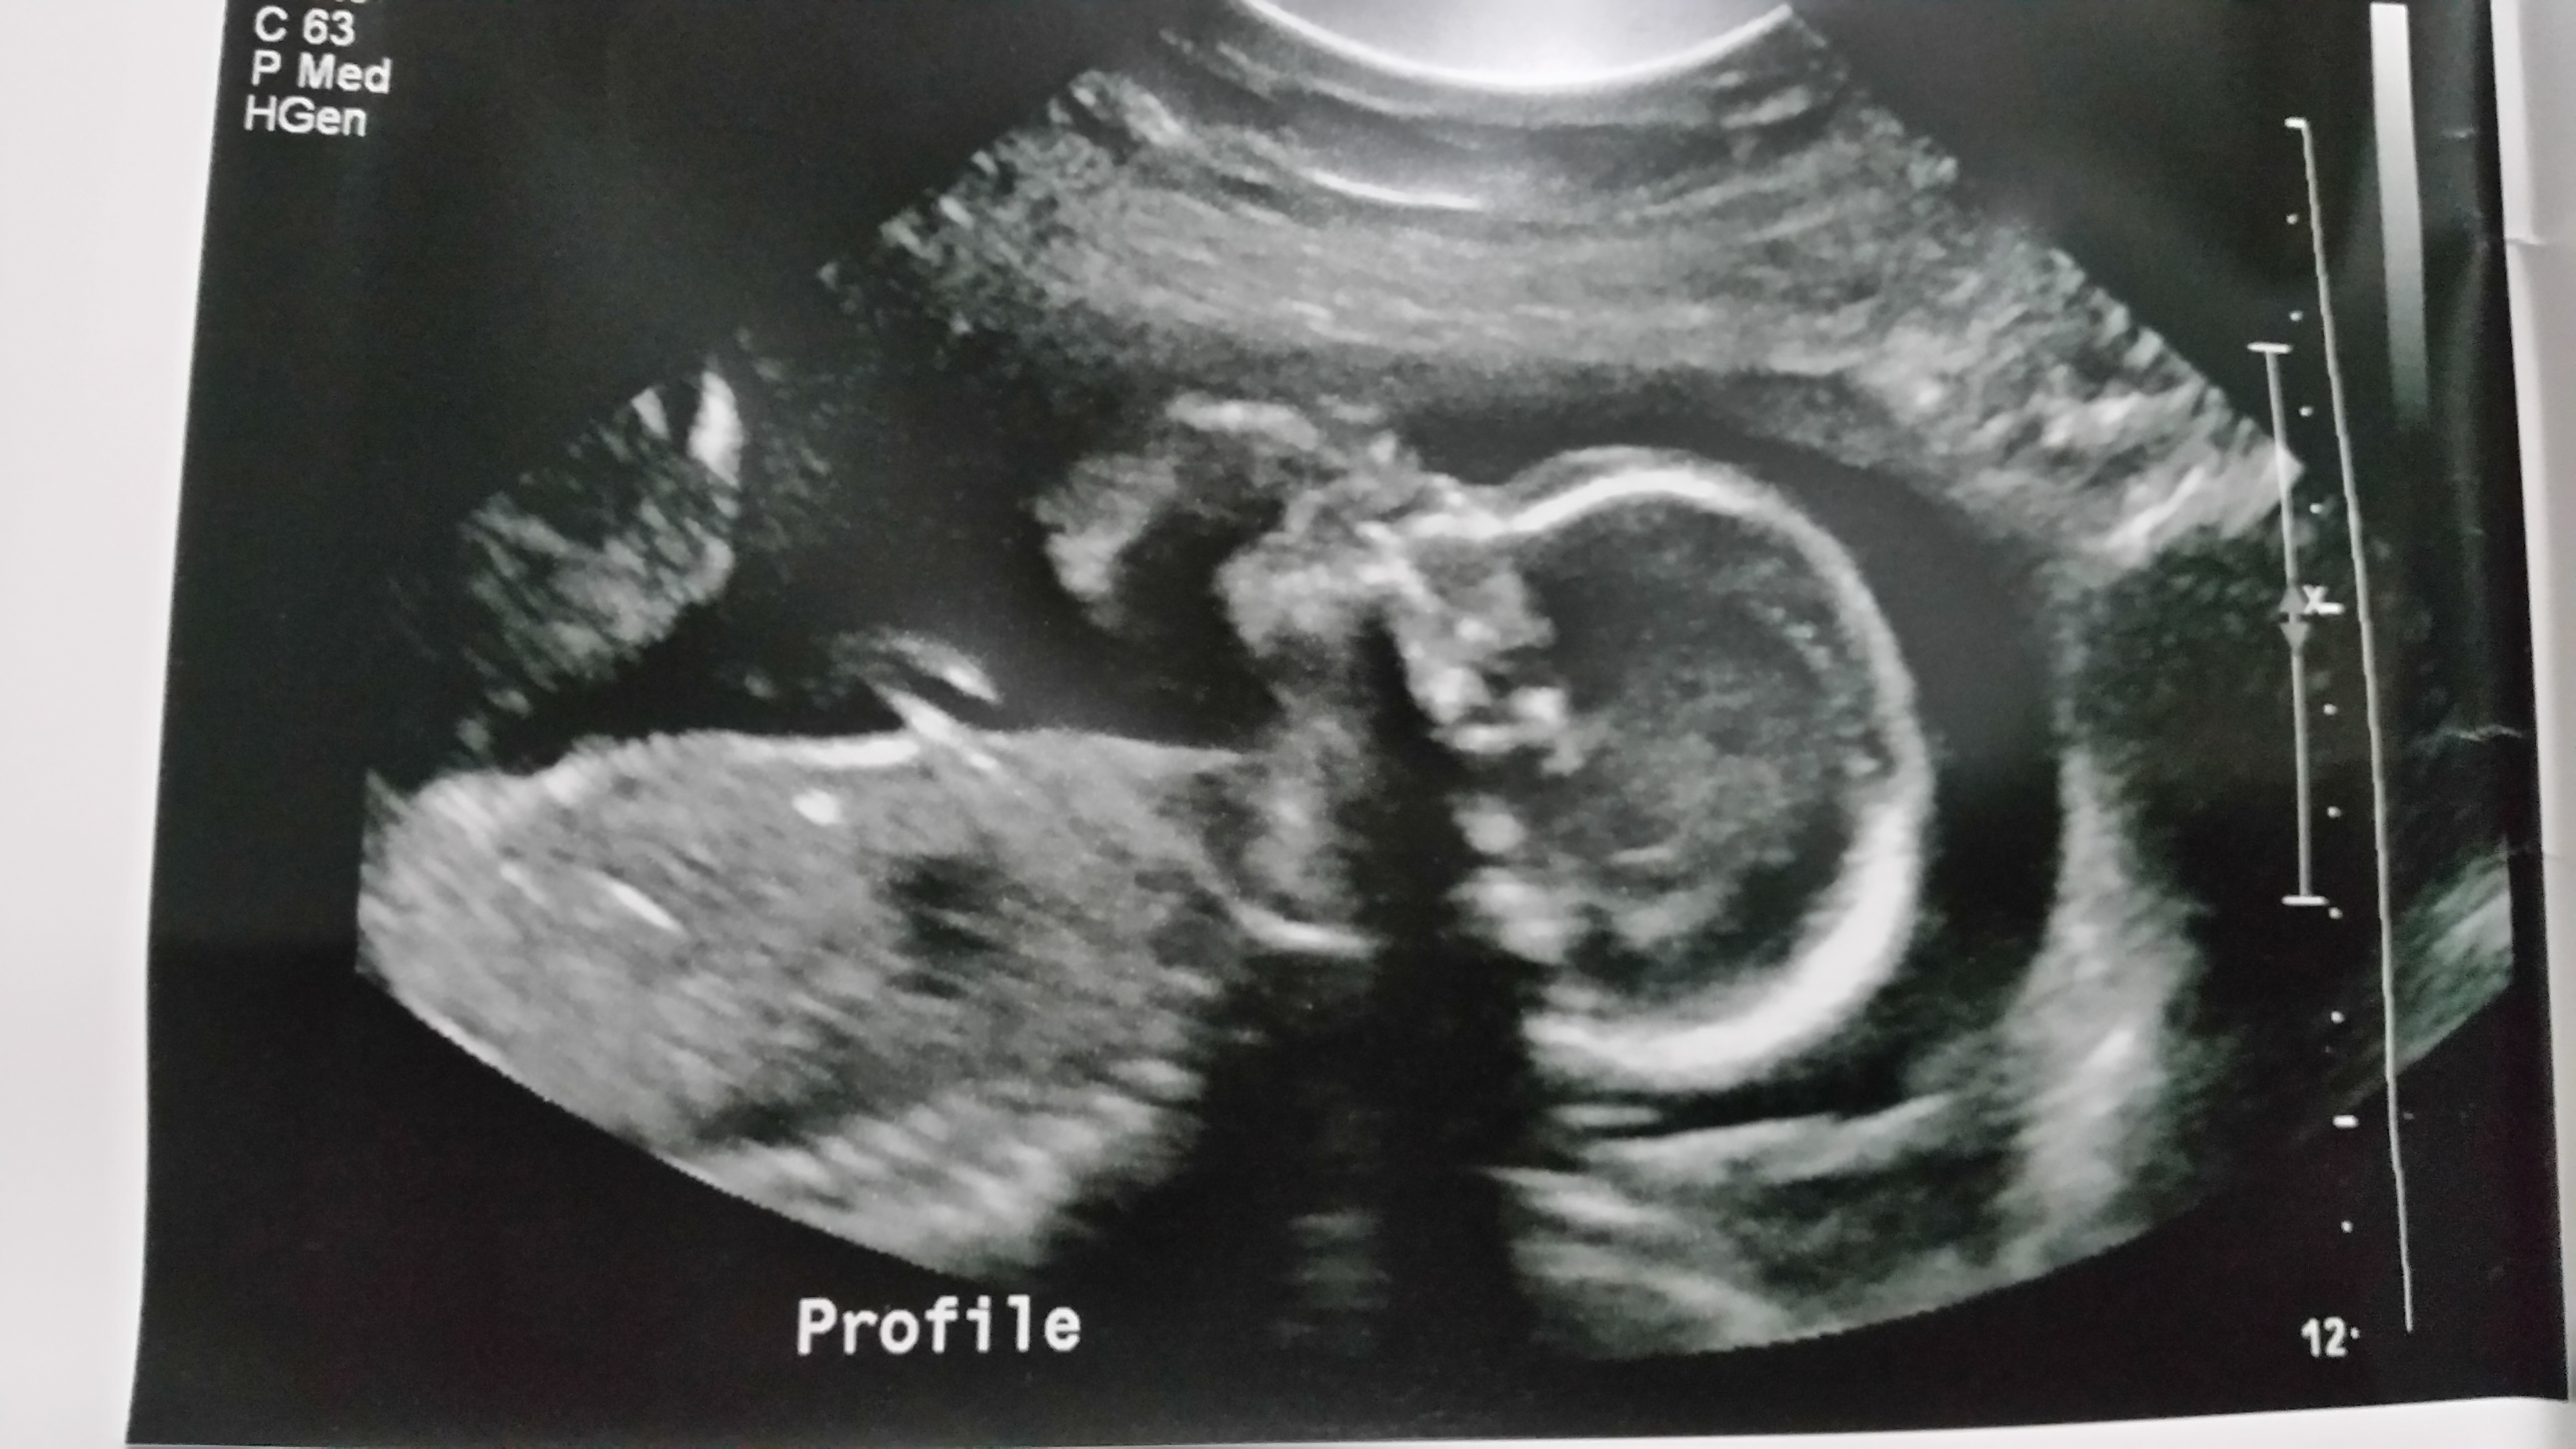

Update i just had my 25 week a 1 day scan please scroll down for latest pics.

I went for my 20 week scan today and came out a bit disappointed I was not provided any potty shots to take they would only give me these 2 pics. The lady did say she thinks it's a girl but can't confirm and based on her inexperience I'm skeptical to say the least .

I'm looking to go get another scan and hopefully get better pictures, in the mean time please let me know your thoughts on these 2 I know they are mostly face but I thought I would ask anyway :)Attachment 33276Attachment 33277